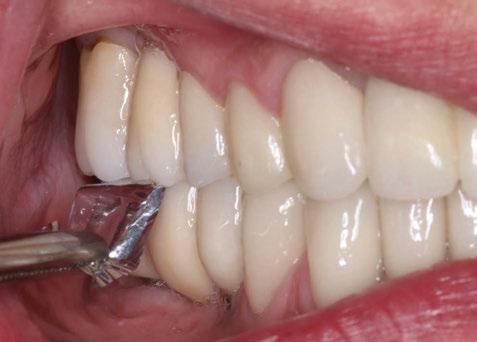

A partir del estudio radiológico y de las imágenes fotográficas podemos observar edentulismo de 17, 15, 14, 12,

Figura 1a. Foto intraoral frontal inicial.

Figura 1b. Foto intraoral lateral izquierda inicial.

Figura 1c. Foto intraoral lateral derecha inicial.